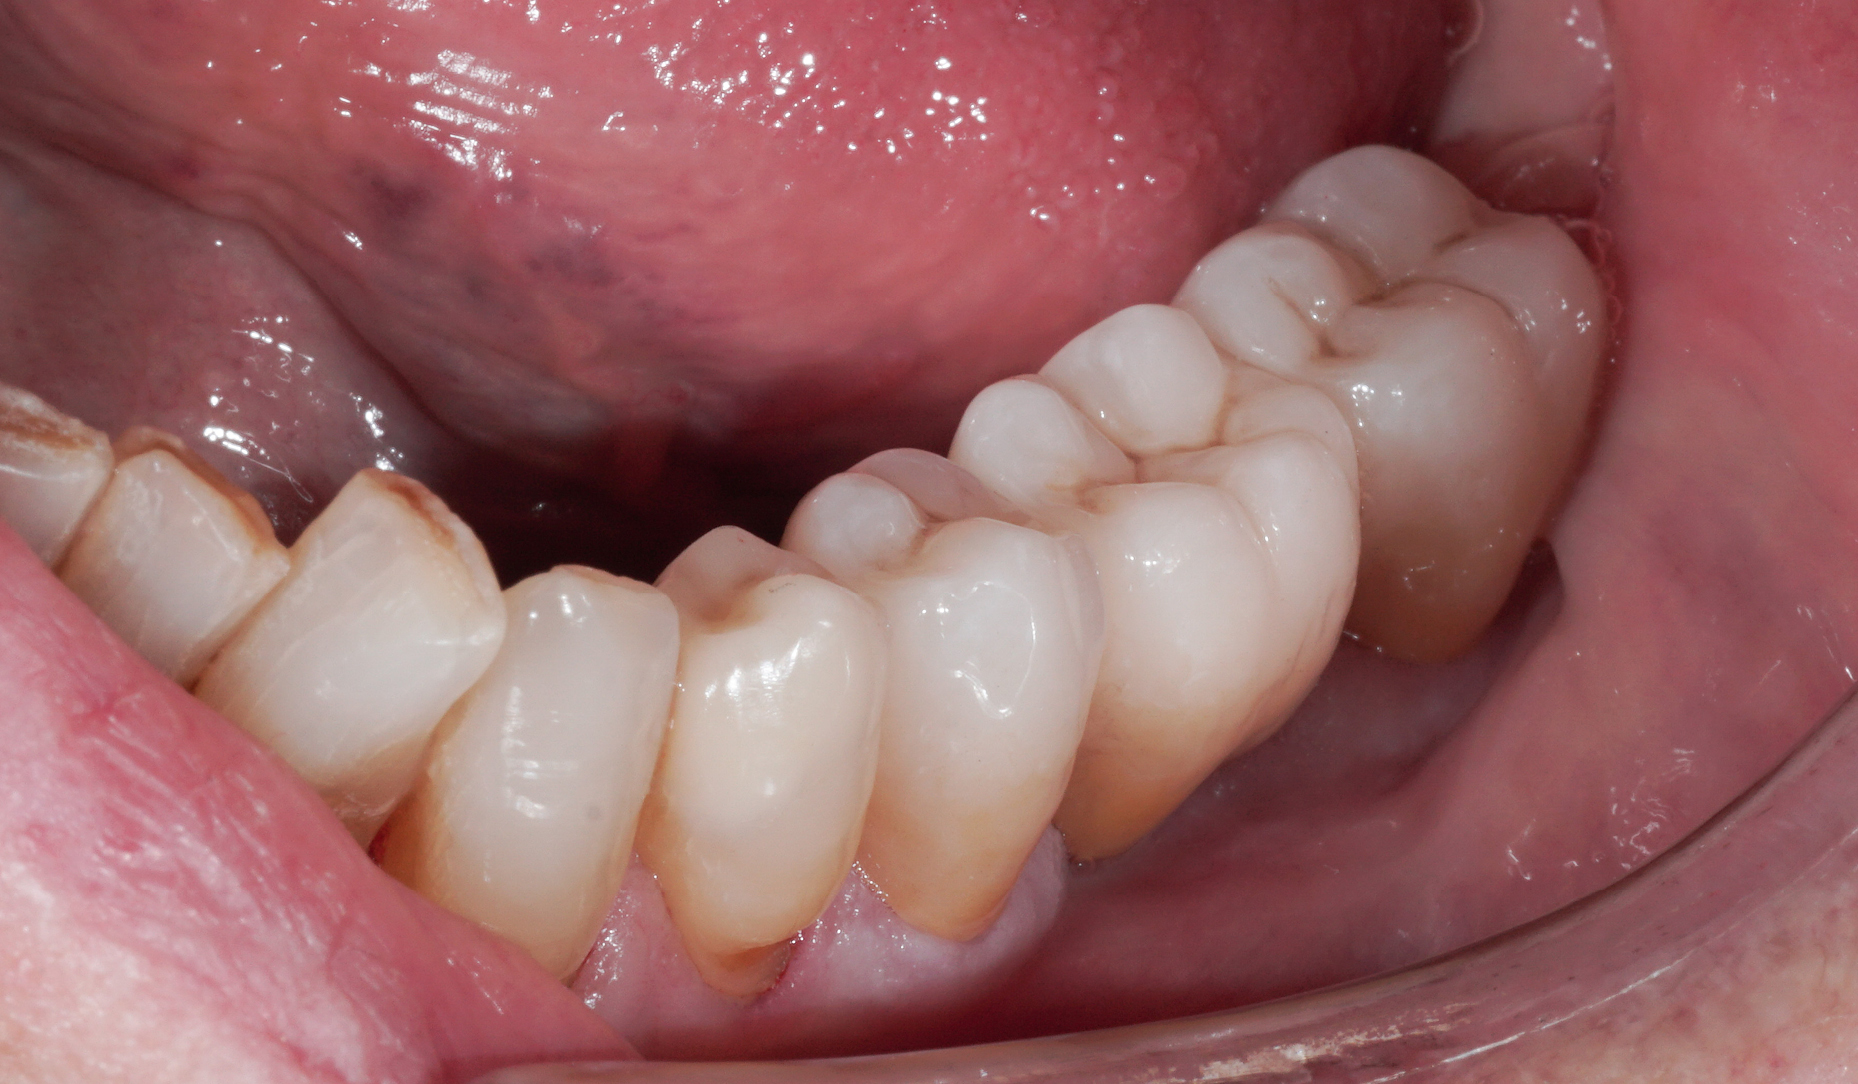

Ryc. 11. Stan kliniczny po odbudowie zębów za pomocą nakładu z dwukrzemianu litu i mostu z tlenku cyrkonu KATANA™.

Ryc. 12. Nakład onlay i most na swoim miejscu w jamie ustnej (po adhezyjnym osadzeniu na PANAVIATM V5 i samoadhezyjnym cementowaniu na PANAVIATM SA Cement Universal).